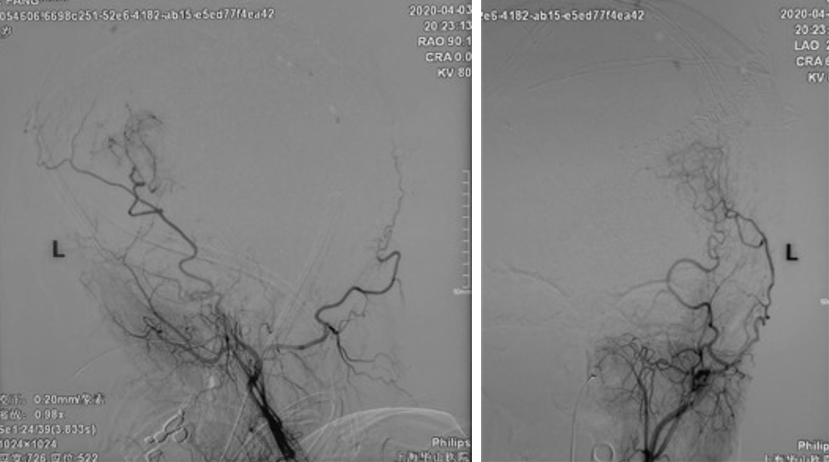

术后DSA

AN消失

Graft patency

GCS 15,语言及肢体功能良好。

有观点认为此类动脉瘤可以保守治疗,因为较小的脑室旁动脉瘤可能自发消退,但同样存在保守治疗的病例预后不佳[1-4]。深部动脉瘤通过血管内介入治疗往往能取得较好的疗效,治疗能否成功关键取决于载瘤动脉直径[5]。血管内栓塞通常是烟雾病患者脑室旁动脉瘤的首选方案,因为可以避免开颅手术对脑实质的损伤及相关的缺血事件发生[1]。在一项病例系列研究[6]中,血管内栓塞成功治疗了7例(88%)烟雾病伴脑室旁动脉瘤且无围术期并发症,其中6名患者在出院时完全康复(75%)。然而,烟雾病患者载瘤动脉往往十分迂曲,且动脉瘤容易破裂[5]因此血管内治疗往往充满挑战。显微手术夹闭是动脉瘤的传统治疗方法,但在治疗深部动脉瘤时,术中破裂的风险可能更高。微创手术如小骨窗和神经内镜已用于治疗颅内深部病变,并取得了不同程度的成功。

在本例病例中,针对脑室内动脉瘤,我们首选血管内治疗栓塞脑室旁动脉瘤,因为血管过于迂曲尝试失败。术后出现脑室内出血,于是启动备选方案,急诊在磁共振导航下通过endoport辅助进行动脉瘤切除,同时部分清除脑室内血肿并放置脑室外引流,降低远期脑脑积水的风险。随着神经内镜的普及,深部的脑血管病变的治疗方案有了更多的选择,而充分的术前评估与周全的手术方案规划是手术安全与成功的基石。